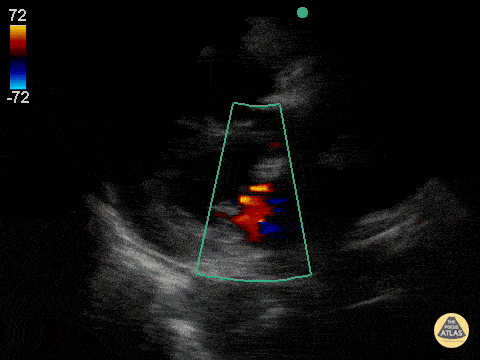

Valve Regurgitation

Tamponade

• Pericardial Effusion +

• RV collapse in diastole

• RA collapse in systole

• Pulsus paradoxus in TV/MV inflow

• IVC dilation